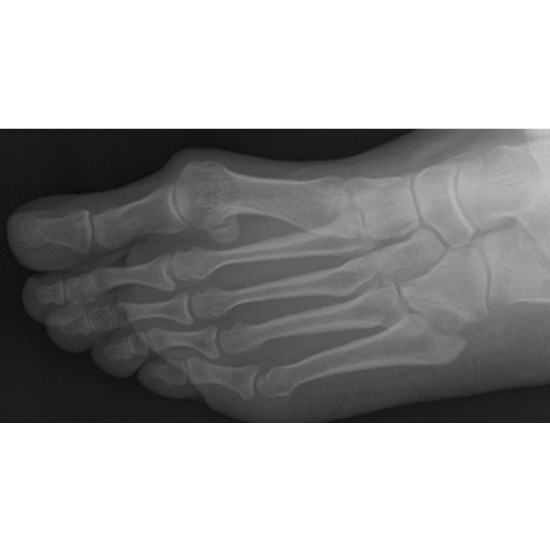

(A) Nutcracker fracture of cuboid was seen on an anteroposterior Walking Boot For Cuboid Fracture “cam boot,” aka controlled ankle motion boot, and “walking boot” are often used interchangeably, but they can refer to different. The boot should be used for two to six weeks when walking; Keep in mind that walkers are usually just. These fractures almost always heal well with time and therefore follow up clinic appointments are not. Please start to walk. Walking Boot For Cuboid Fracture.